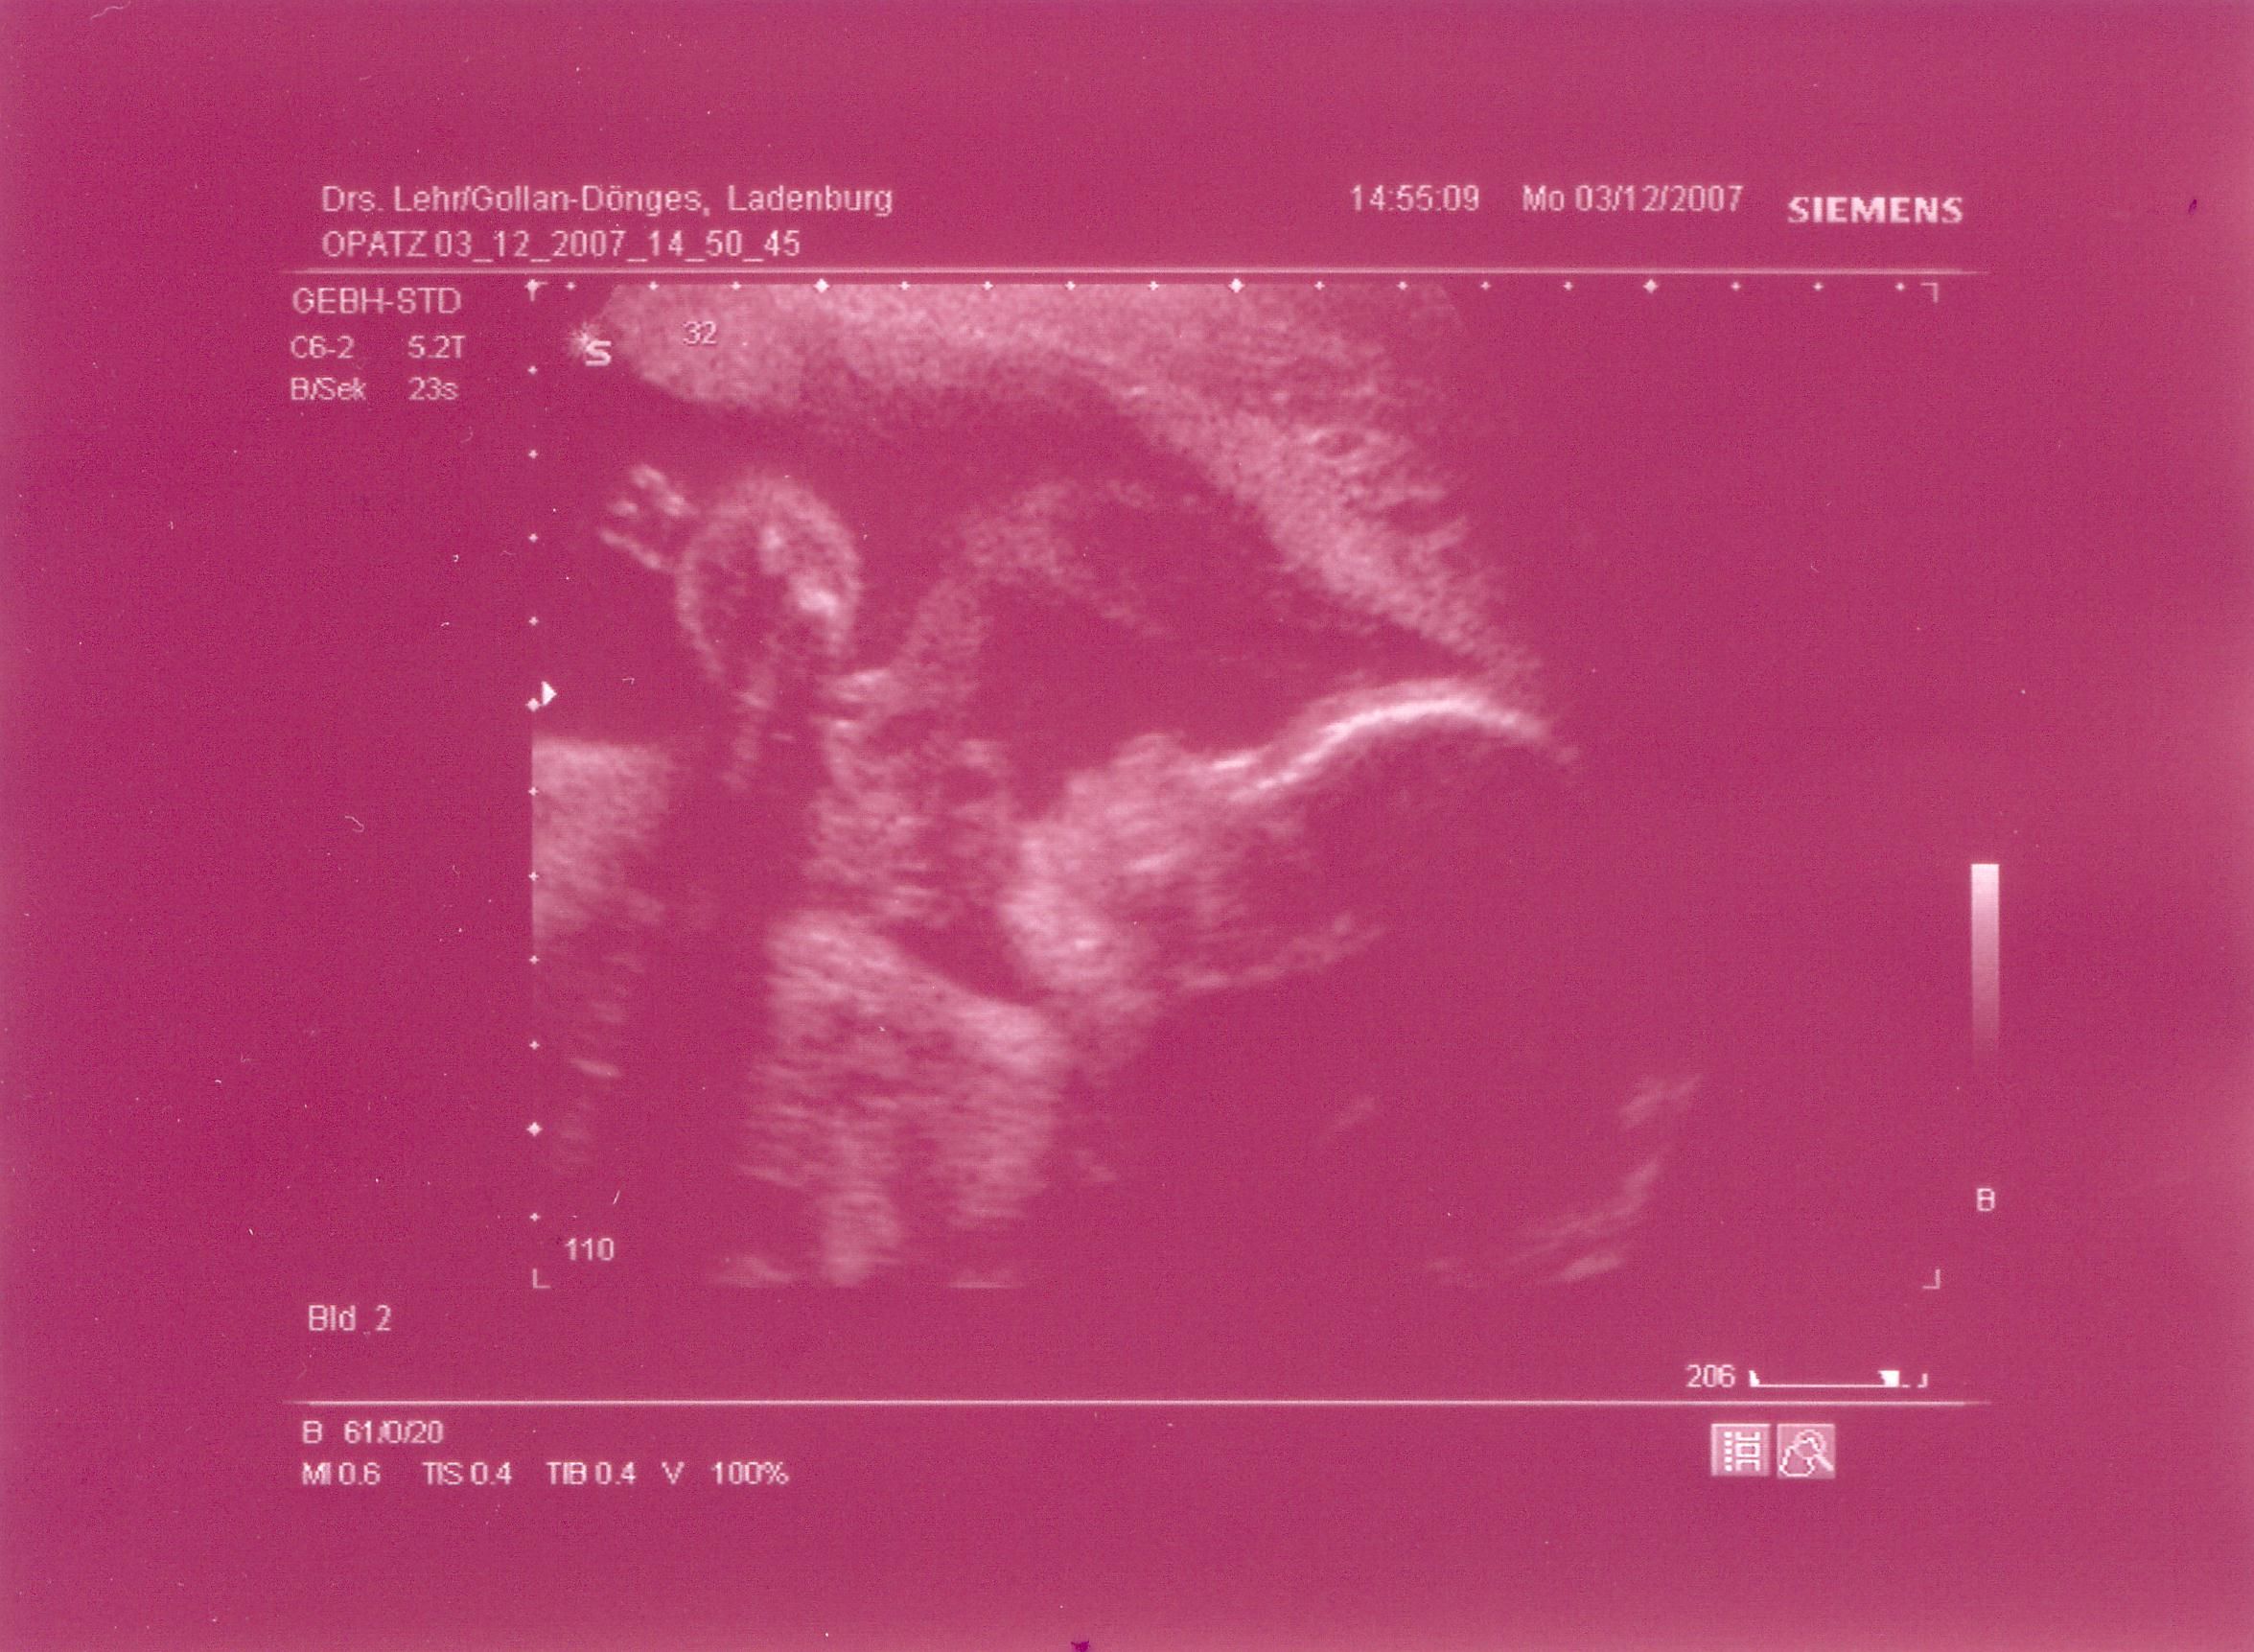

Dann zum US.....................und es sieht alles gut aus

Uuuuuuuuuuuuuuuuuuuuuuuuuuuuuuuuuuuuuuuuuund wir bekommen :

EIN MÄDCHEN

Oh wenn ich könnte, würde ich sie knutschen unsere kleine Schnute

so süß sah sie heute aus und wir haben sie wohl aufgeweckt denn sie hat sich erstmal ganz genüßlich gestreckt.

Köpfchen liegt nach untern und drückt mir mächtig auf die Blase.

Allerdings ist Sie immer noch etwas zu zart ...gerade mal 560g. bringt Sie auf die Waage

dafür hat Mama kräftig zugelegt...wieder 2kg. mehr auf den Rippen

Hier auch ein neues US-Bild ....ich frag mich was da für kugelige Sachen an der Hand sind